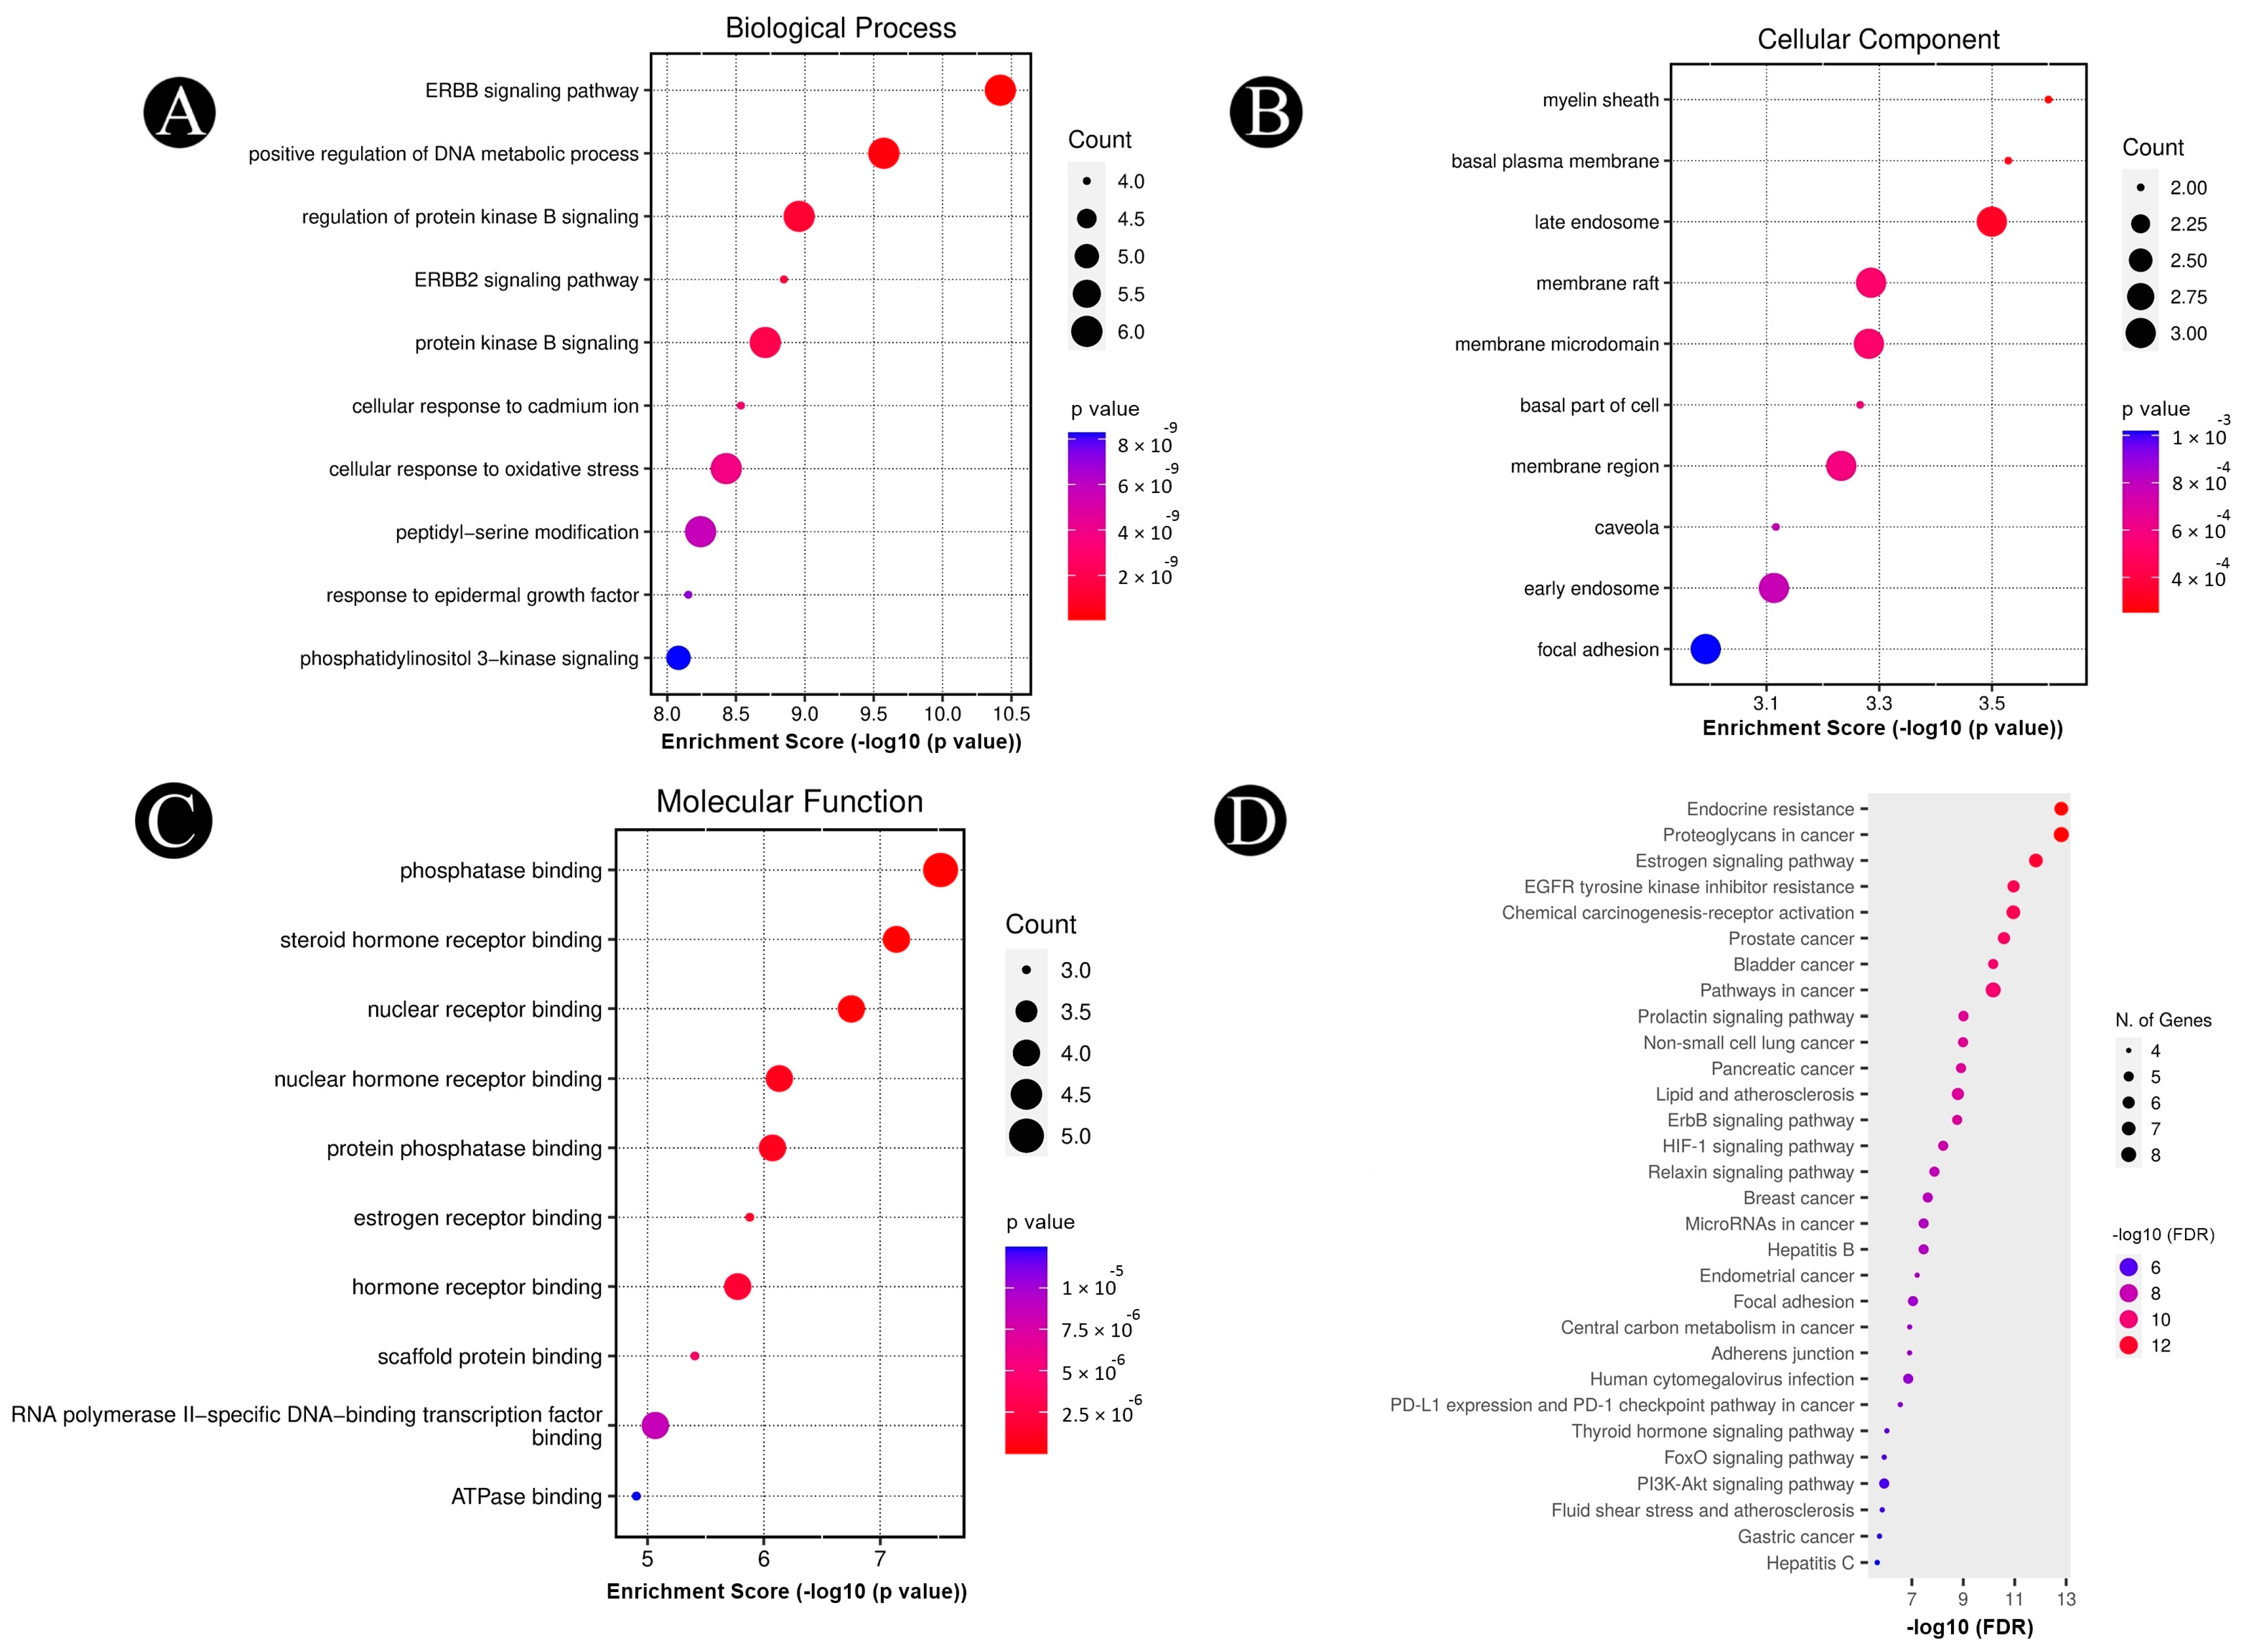

2.4. Analysis of Pathways and Functional Enrichment

4.5. GO and KEGG Pathway Enrichment Analysis